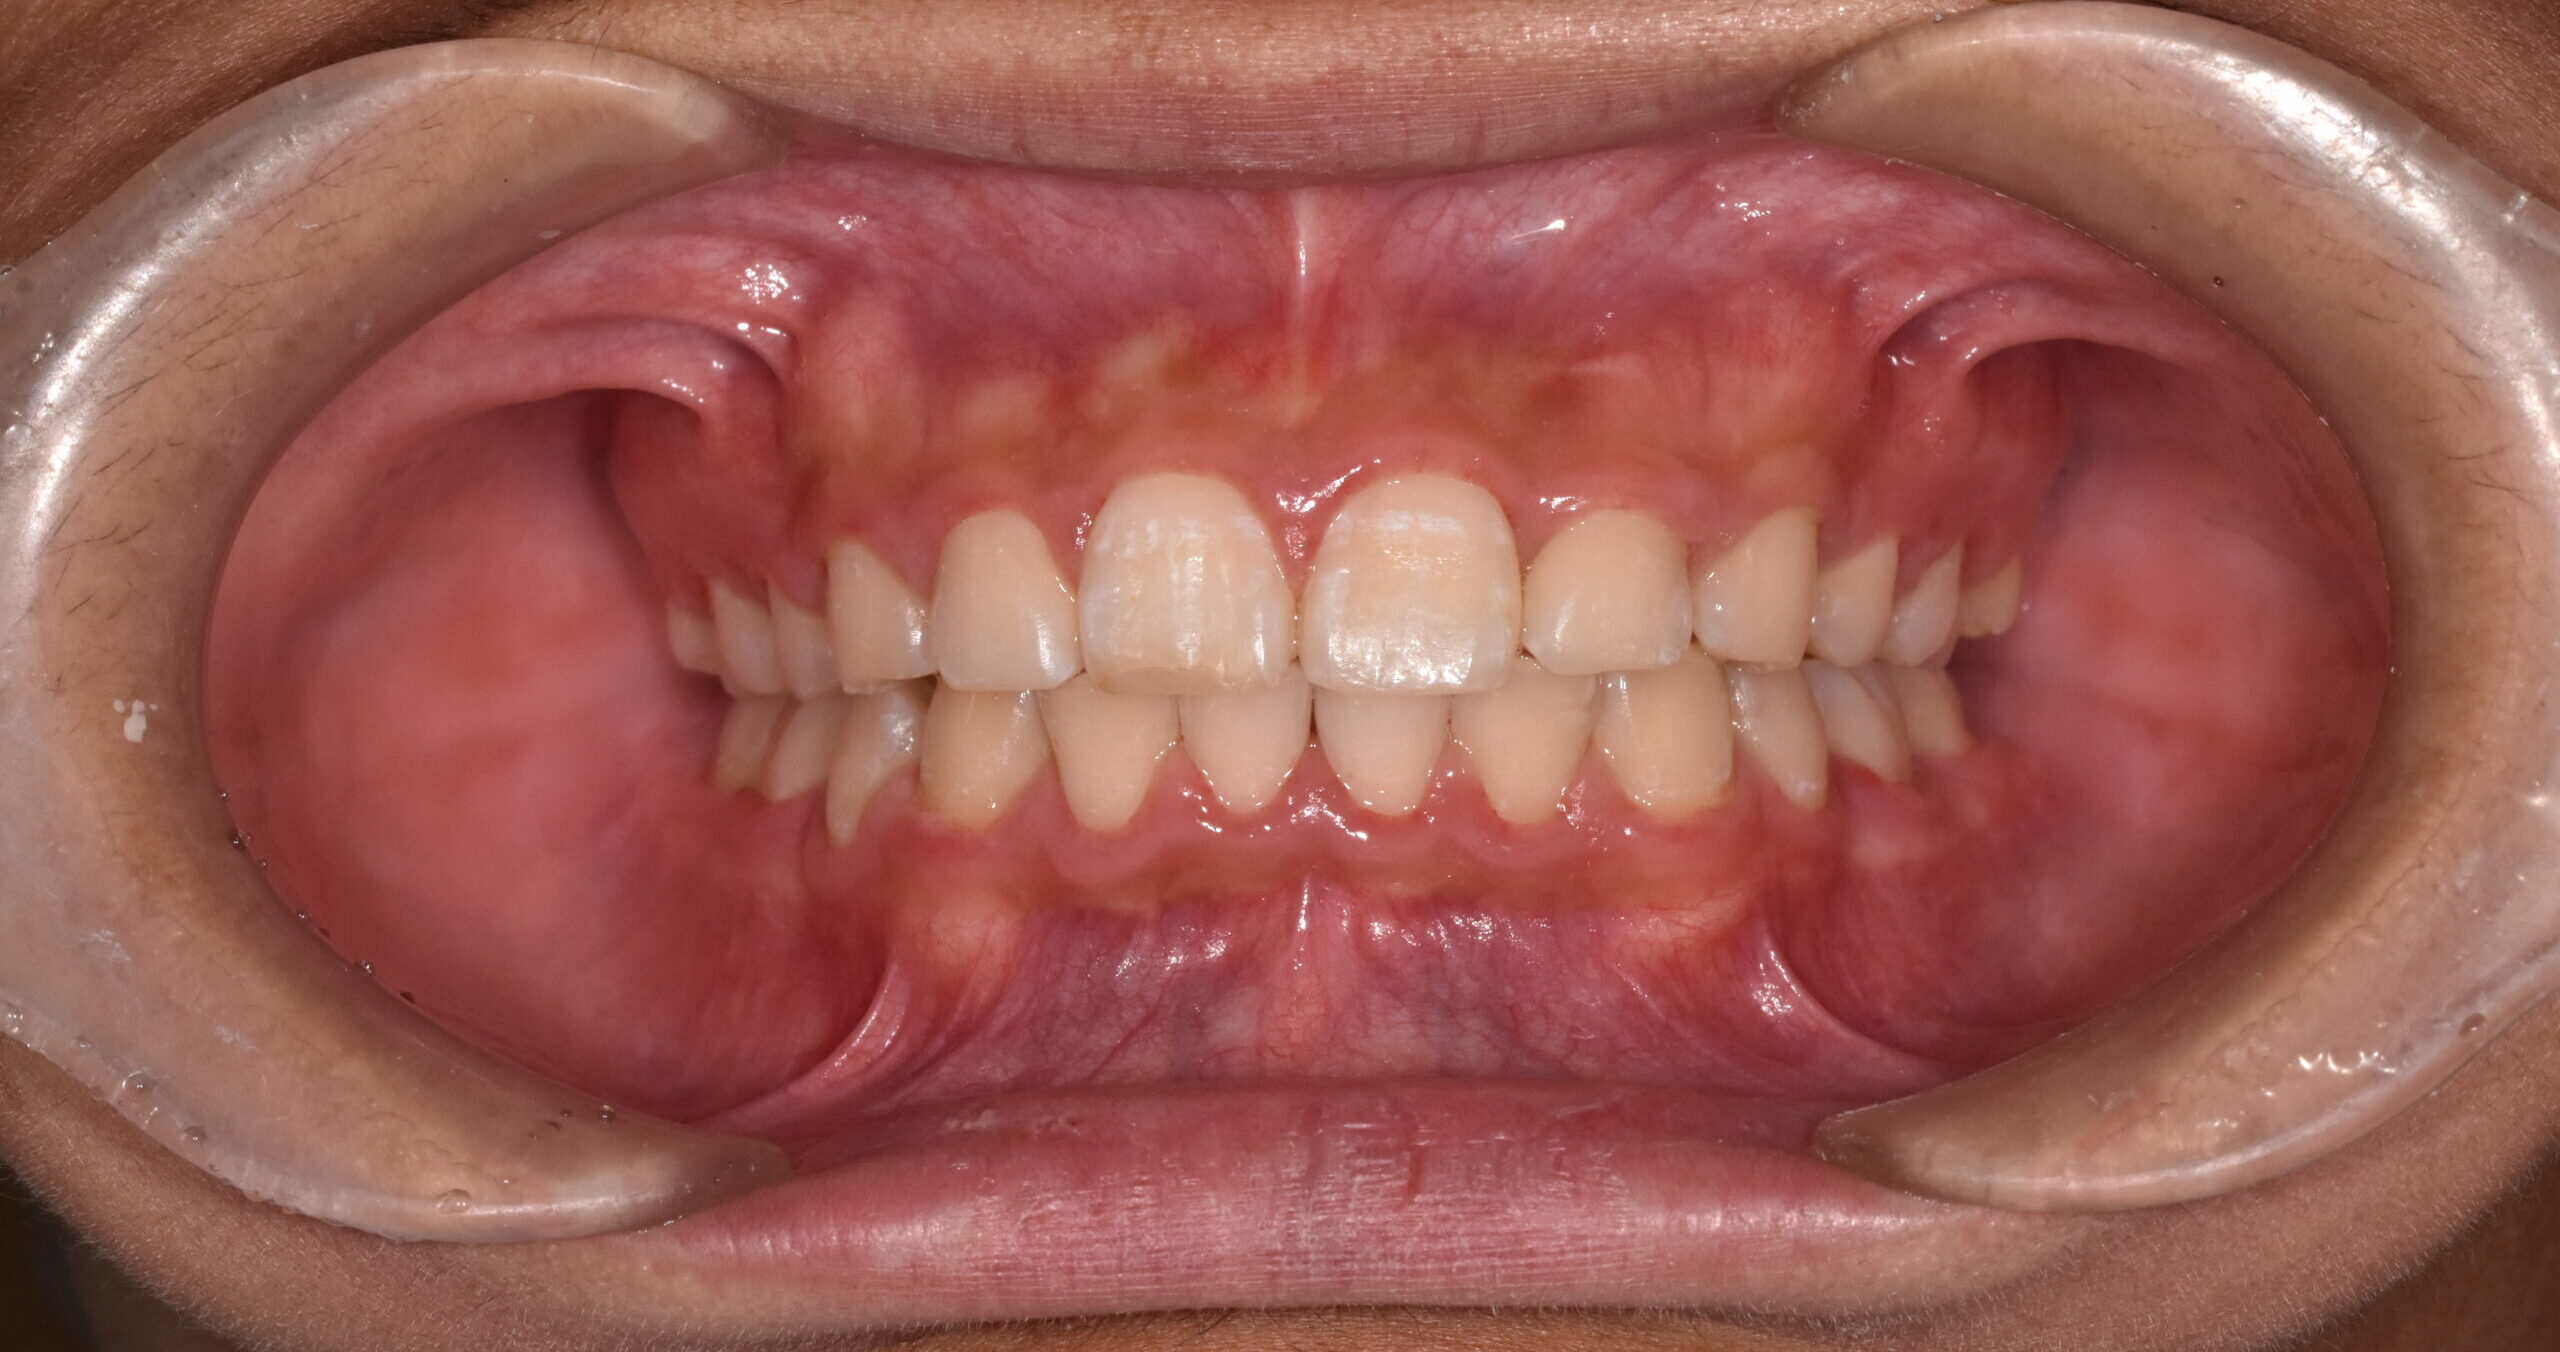

過蓋咬合・叢生 13歳男性

13歳9ヶ月 男性

治療後

【診断】叢生、過蓋咬合

【治療方法】上下両側第一小臼歯抜歯、ワイヤー治療期間3年間、上顎口蓋にTPA(トランスパラタルアーチ)を行いました。